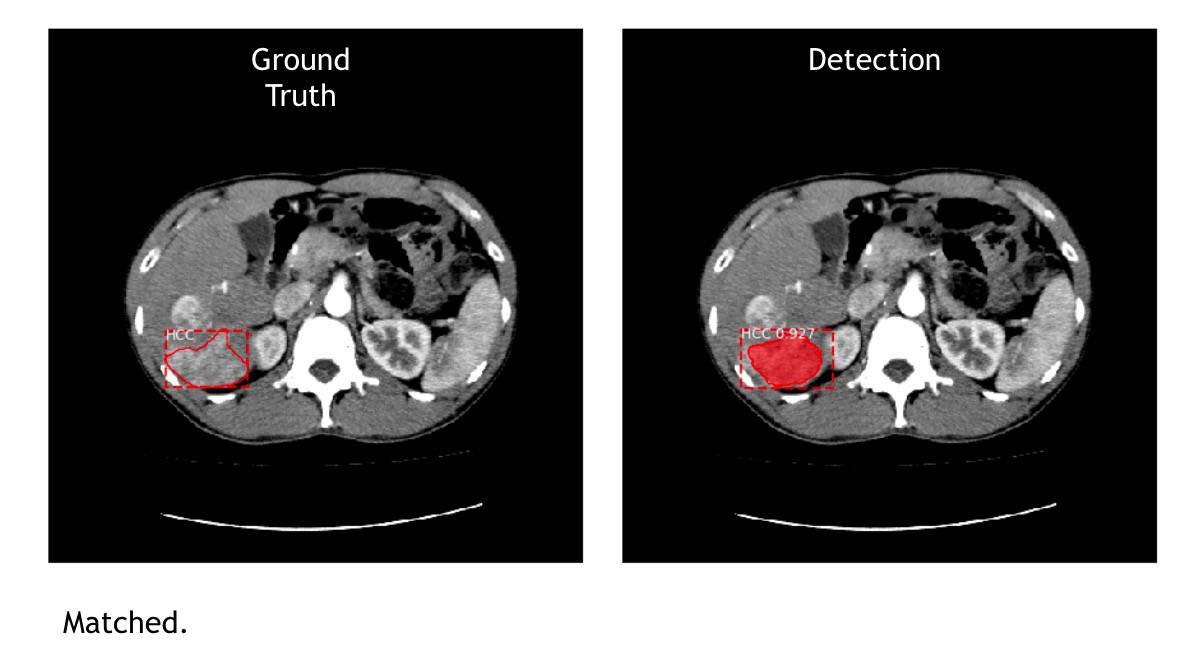

先用下方的肝脏 CT 图片来解释,左边 Ground Truth 图是传统的做法,就是医生看片子,把肿瘤的位置、大小框出来。右边 Detection 图是 AI 侦测的结果,上头显示 HCC(肝细胞癌 Hepatocellular Carcinoma,简称HCC) 0.977 ,数字指的是机器下判断的自信程度(与准确率无关,只是机器在做判断时对答案的自我评估)。

图|左图是医生手动标示,右图是 AI 侦测的结果,HCC 0.977 数字是机器下判断的自信程度。(图片来源:CMUH人工智能医学诊断中心

图|左图是医生手动标示,右图是 AI 侦测的结果,机器都能找出肿瘤位置及大小。(图片来源:CMUH人工智能医学诊断中心)